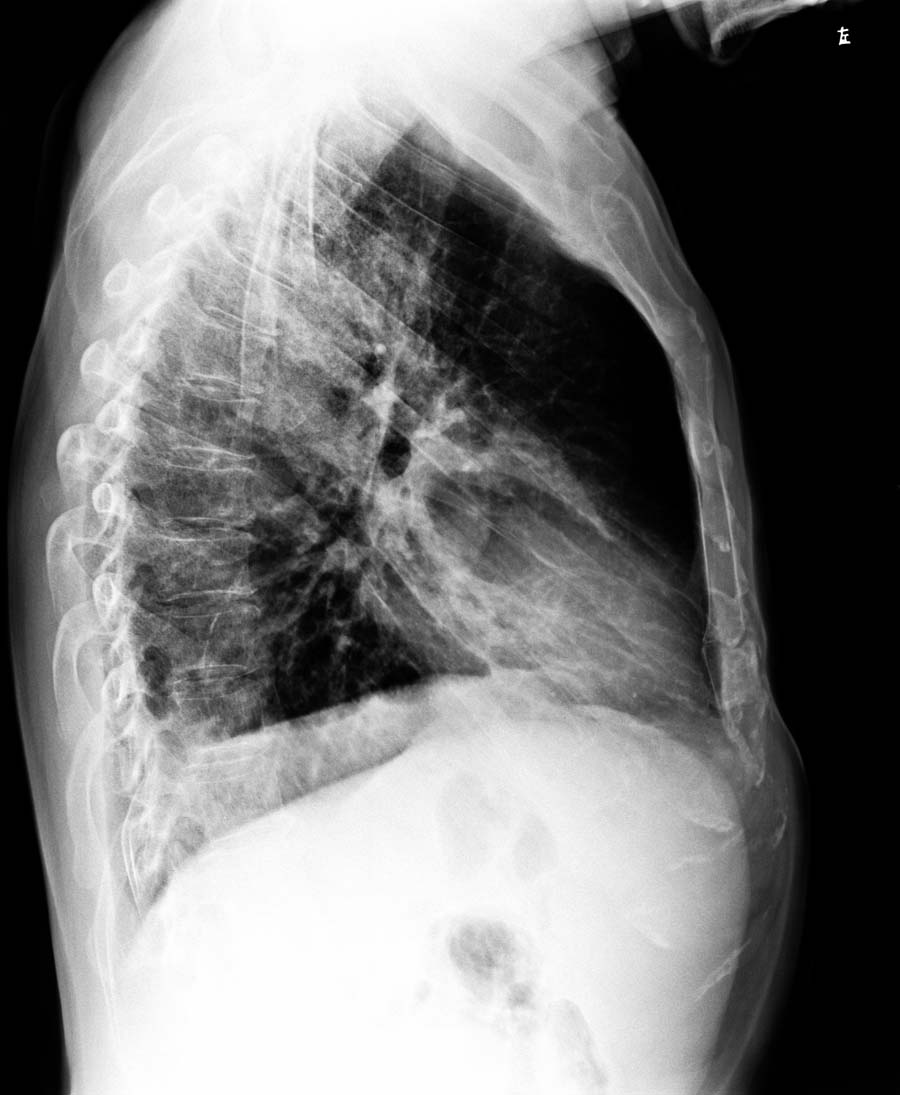

版主的侧位片是右侧位吧?不好意思.